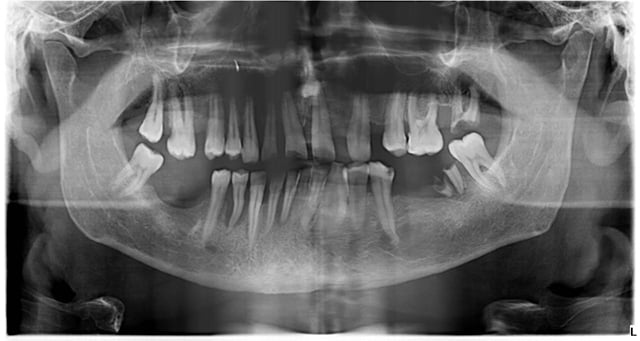

- КТ (конусно-лучевая компьютерная томография) для оценки объёма кости, положения пазух, нервов, толщины стенок.

- Планирование позиции имплантата (часто в цифровом виде), иногда изготовление хирургического шаблона.